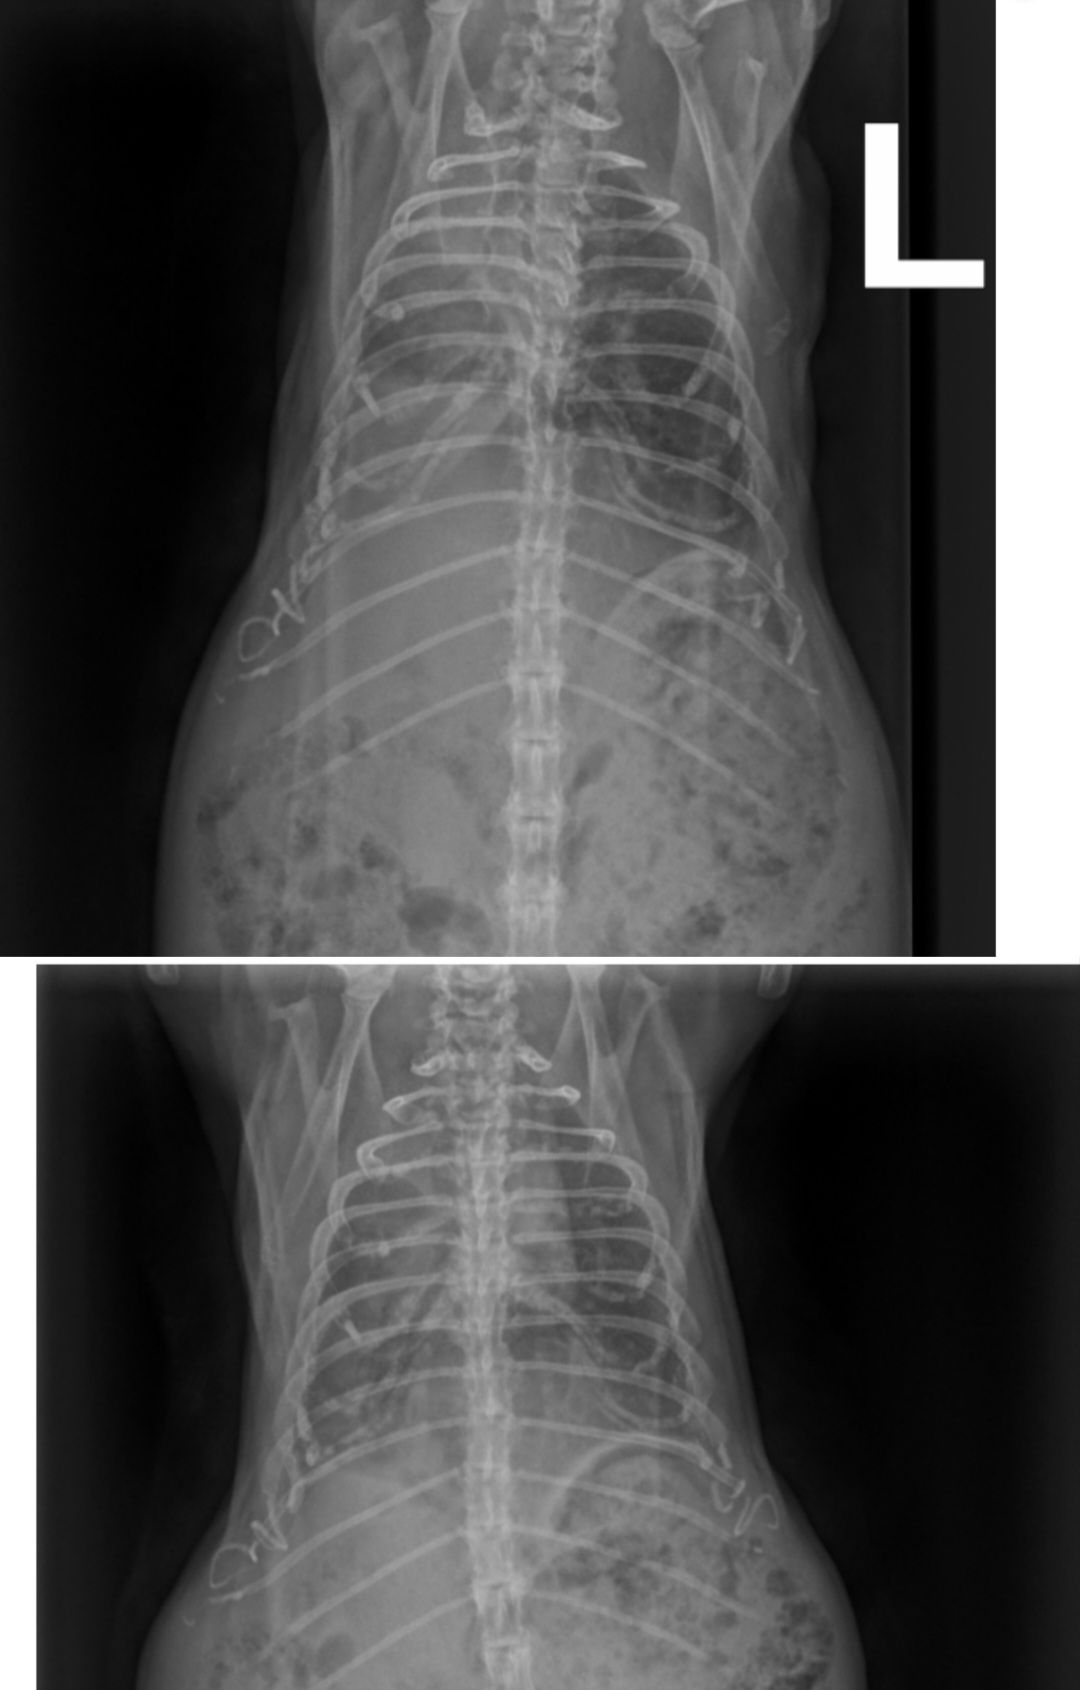

Auf dem ersten Bild fällt der große Unterschied zwischen dem auf dem Bild links zu sehenden Lungenflügel und dem anderen, weniger geschädigten auf. Johnny schien dort nach oder bei dem Einatmen aufgenommen worden zu sein.

Auf dem zweiten Bild schien er gerade ausgeatmet zu haben. Daher ist auch in dem besseren Lungenflügel weniger Luft als vorher. Aber der Unterschied zwischen bei Lungenflügeln ist geringer geworden. Zudem ist auf der auf dem Bild rechten Seite der Lungenflügel wieder gleichmäßiger "befüllt".

Die Heimtierärztin war heute nur im OP da, aber ich konnte Fienchen heute früh direkt zum Röntgen vorbeibringen und sie hat sich die Bilder kurz angeschaut und einen ersten Plan aufgestellt. Leider konnte ich nicht direkt mit ihr sprechen, aber morgen sollen wir wiederkommen, dann macht sie noch einen Ultraschall. Neben einer Aufgasung ist da nämlich noch eine Struktur im Bauchraum, die sie sich im Schall ansehen will.

Hat das von euch schon mal jemand gesehen? Könnte das die Blase und somit ein Stein sein? Und rechts unten davon auch was komisches(?)Ach Mäuschen... 🥺

Rechts unten würde ich zur Blase zuordnen und deshalb auf Blasengries oder Blasenschlamm tippen. Das oben könnte evtl. ein riesiger Blasenstein sein.

Das Auffällige auf dem Röntgenbild soll wohl eine Kalkablagerung sein (wo/von was konnte ich nicht mehr fragen) und vermutlich nur ein Nebenbefund, aber nicht die Ursache für ihren Zustand.

Guck mal das Röntgen-Bild von dem Kaninchen an. Ich finde die Blase sieht farblich ähnlich aus und bei diesem Bild soll es Harngries sein.

Lunge im Röntgenbild massiv angegriffen (ggf Entzündung aus Maul in die Lunge gewandert?), stark aufgegast, Untertemperatur, schwere Atmung.